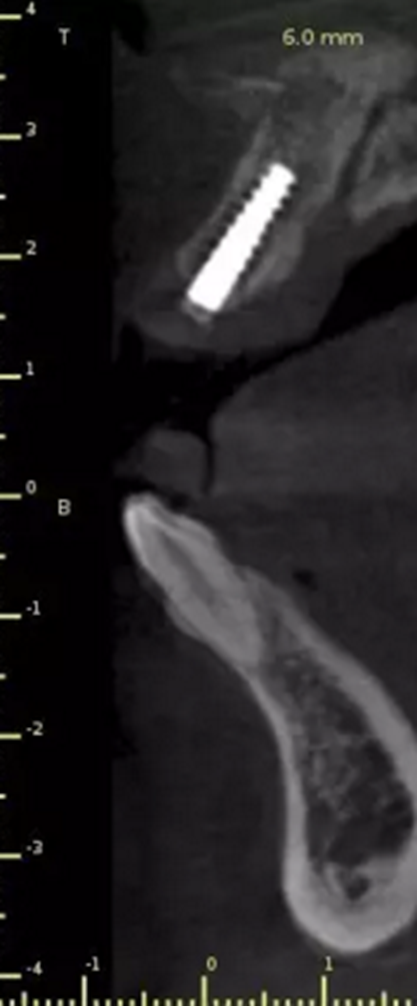

1.術(shù)前CT

術(shù)后CT